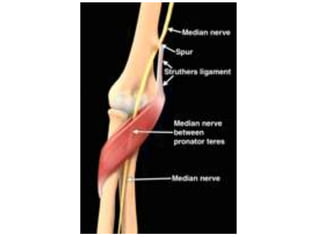

Medial Nerve

1. Supracondylar process

2. Ligament of Struthers

3. Lacertus Fibrosus

4. Heads of PT

5. FDS aponeurotic arch

Pronator Syndrome

• Reduced sensation with

repetetive rotation of forearm

• Includes palmar cutaneous

branch

• Fatigue of forearm muscles

• Tinels positive in proximal

forearm NOT at wrist

• Resisted flexion of long and ring

fingers may cause forearm pain

• Resisted elbow flexion + forearm

• Nb-coexisting golfers elbwo